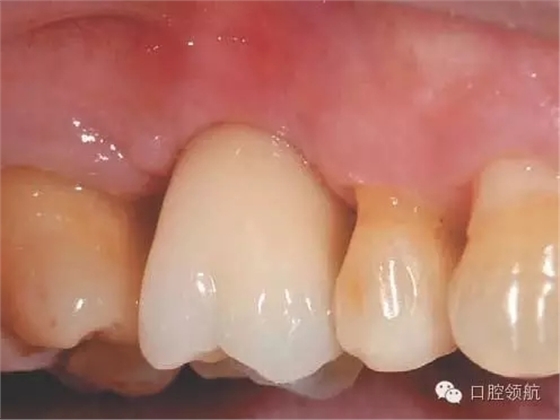

圖2 拔牙后4周,牙齦上皮完全覆蓋拔牙窩。

圖8 術(shù)后16周戴入上部修復(fù)體。